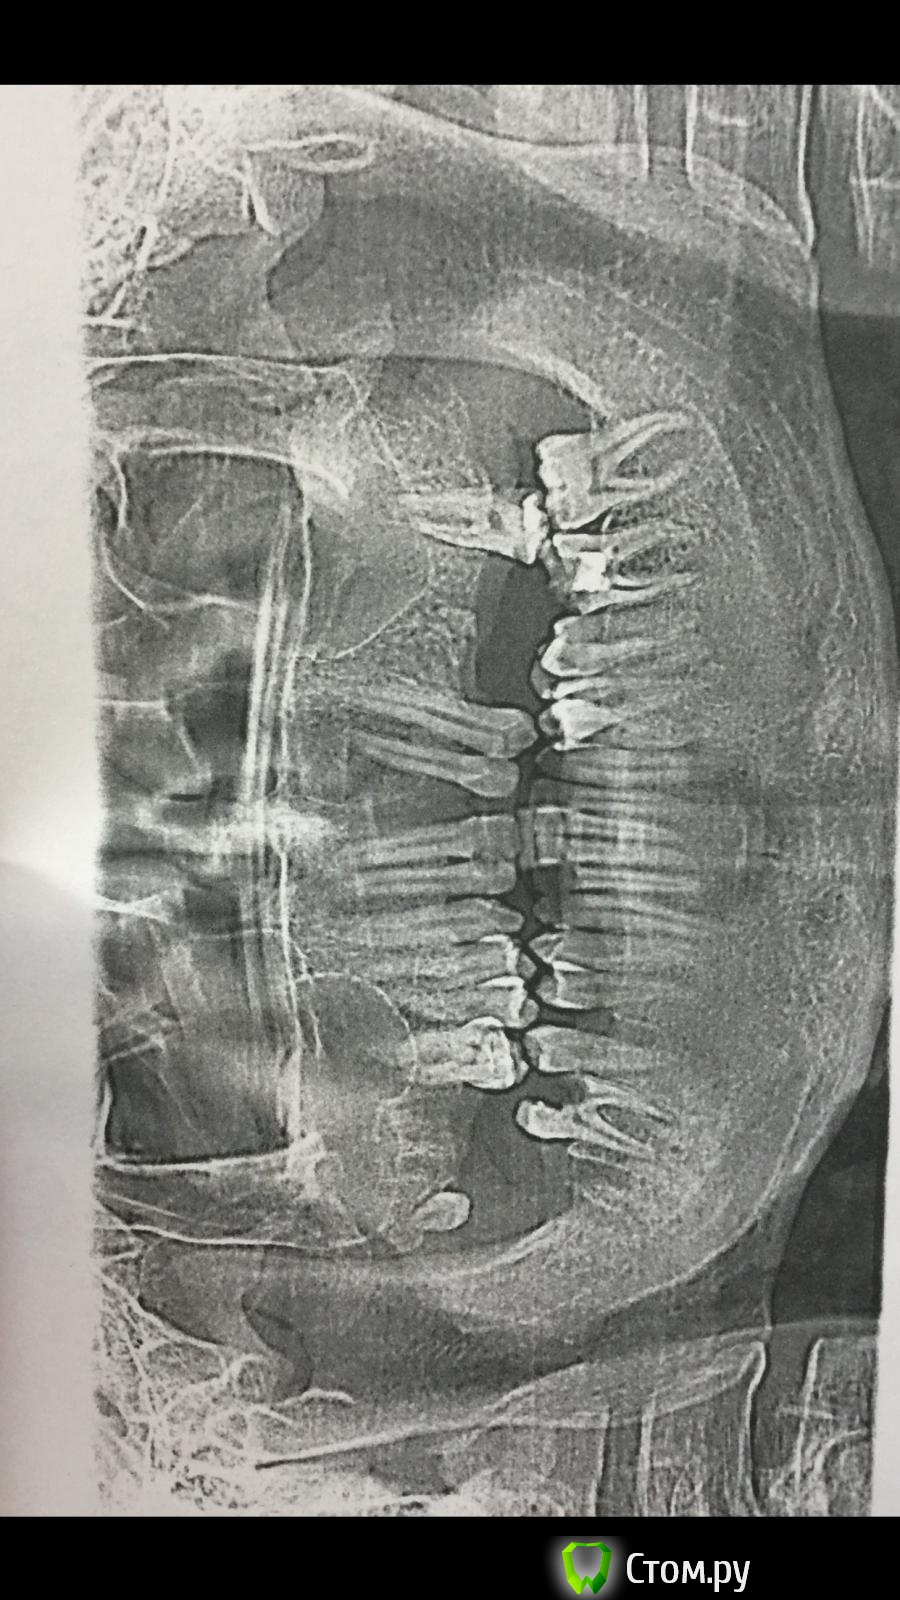

solovushka1988 Опубликовано 23 октября, 2014 Поделиться Опубликовано 23 октября, 2014 Друзья,Я страшный сладкоешка, и по этому зубам моим было очень плохо.Я хорошо помню того стоматолога, который отбил всякую охоту когда либо лечить зубы, это правда страшная история и мне никто до сих пор в нее не верит, но с 11 лет я больше никогда не обращался к стоматологам (простите за флуд) теперь по существуЭтот (прикрепленный снимок сделан на кануне удаления еще 4 зубов)Но в общем числе я удалил уже 19 зубовСлева внизу мне удалили 5-6 и за ними вне комплектные 5-6 (дырень была сдоровенная даже швы) (их правда нужно было удалить 5-6 были пнями а вне комплектные были в аккурат под языком) (ранее уже удалил много внекомплектных) в общей сложности 8 лишних зубов было удалено и 2 осталось прошу обратить внимание на то, что у меня буквально 7 дней назад удаленны 7-8 в верху справа но растет еще один девятый зуб мудрости (на самом деле 11 потому что 5-6 тоже в этой челюсти дублировались и сейчас заживают лунки)Внизу слева были удалены 8 и 6 остались осталась сломанная 7 и внекомплектный на месте шестерки по форме напоминающий 4 (эта внекомплектная четверка ) выросла в аккурат между 6-7 тем самым полностью разрушив 6 и 7 (семерку не рву внадежде вылечить и так же не рву семерку слева внизу ( сверху вроде вылечить легко) этот внекомплектный зуб очень неприятно ведет себя в челюсти и ощущаелся чем то лишним как гипс на ноге) но до момента удаления 6киТак вот, у меня был такой план. Сначала удалить все зубы которые невозможно восстановить, Затем, вылечить все остатки, вставить импланты, а затем выровнять все это дело брекетами,Вопросов много, Правильно ли я рассуждаю(про удаление лечение импланты брекеты)?Второй: не помешает ли мне внекомплектный зуб на месте шестерки (лунка от шестерки заживает)( этот зуб значительно меньше и имеет клыкообразную форму?Что мне делать с растущей восьмеркой?Из-за смещения передних зубов у меня изменился прикус(всегда был правильный а теперь нет) реально ли раздвинуть эти передние зубы в верху чтобы вставить единичку? И вообще посоветуйте что мне делать, потому что цель у меня не просто вылечить зубы а востановить 32 зубую улыбку(модно меньше но внекомплектная шестерка видна при улыбке.Почему я спрашиваю здесь а не у терапевтов в больнице, (потому что лечила зубы моя жена и сделали ей так чтобы кушать удобно было но улыбаться ей сложно потому что некоторые зубы меньше чем должны быть(у нее конечно небыло таких проблем но, теперь передние зубы разного размера и исправлять это не хотели потому что пришлось оставлять щель между передними зубами (сказали бы сразу что вам улыбка нужна, сказала врач) вот и я не хочу попать в просак Ссылка на комментарий

Korel Опубликовано 23 октября, 2014 Поделиться Опубликовано 23 октября, 2014 Снимок не идеален.Нужна совместн. консультация ортодонта , ортопеда Но: красное- удалять, зелёное - полечить. Далее ортодонтия, затем ортопедия. С вариациями. http://s42.radikal.ru/i095/1410/fb/e8bc7ff3fb9e.jpg 2 Ссылка на комментарий

solovushka1988 Опубликовано 23 октября, 2014 Автор Поделиться Опубликовано 23 октября, 2014 Спасибо, Снимок не идеален.Нужна совместн. консультация ортодонта , ортопеда Но: красное- удалять, зелёное - полечить. Далее ортодонтия, затем ортопедия. С вариациями. http://s42.radikal.ru/i095/1410/fb/e8bc7ff3fb9e.jpgНу вот я вылечил и дальше ? Имплантироваться, а что делать с некомплектной шестеркой (она слева внизу, на снимке справа) Ссылка на комментарий